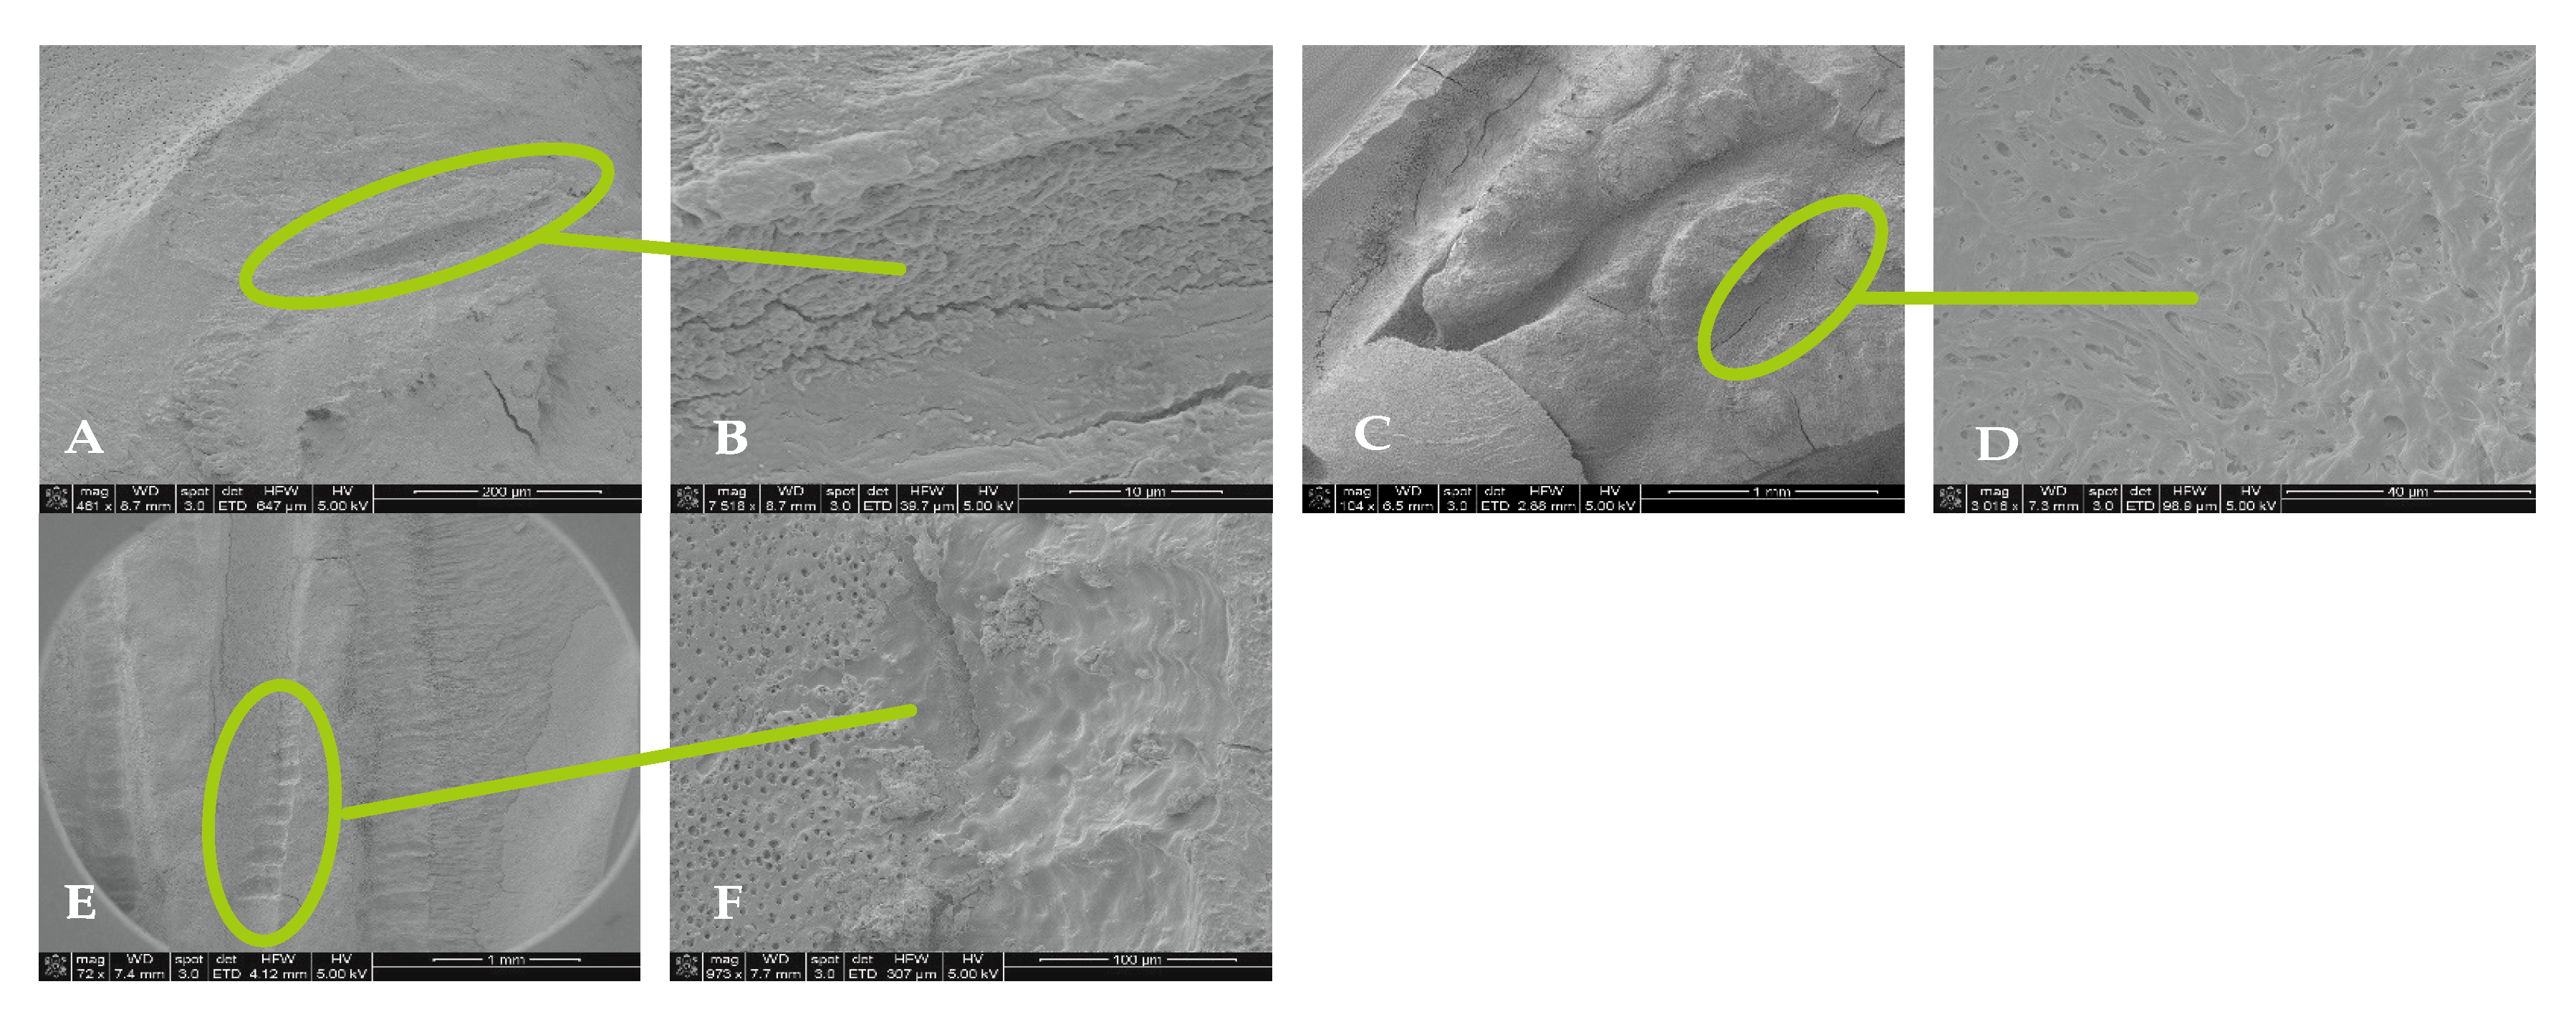

3.3. Scanning Electron Microscopy (SEM)

4.2. SEM Analyses